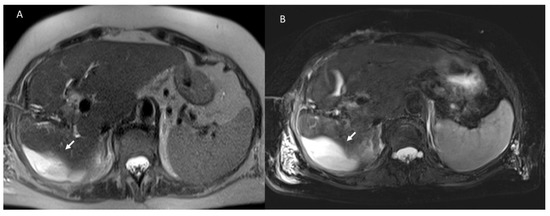

3.1.3. Vascular Thrombosis

3.1.4. Biliary Injuries